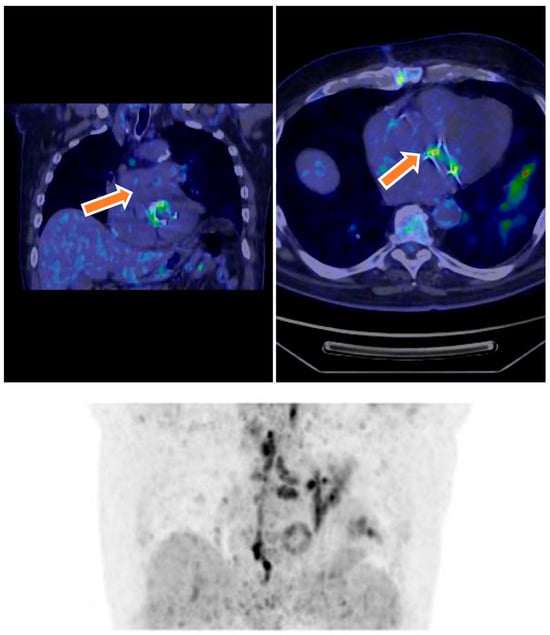

18F-FDG PET/CT showing intense FDG uptake around a prosthetic aortic valve in a 68-year-old male with inconclusive echocardiography. The focal uptake pattern was consistent with active infection and, combined with clinical and microbiological data, led to the diagnosis of definite prosthetic valve endocarditis (PVE) based on modified Duke criteria (Figure 1).

Figure 1. Transverse 18F-FDG PET/CT images show an infected prosthetic aortic valve. Culture after valve removal was positive for Candida albicans.